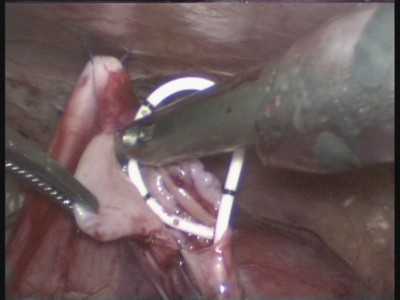

Последние 10 лет мы выполняем операции по поводу гидронефроза из лапароскопического доступа.Успешно оперированы более 185 больных

Рис.12. Лапароскопическая операция.

Рис. 13. Установка внутреннего стента в мочеточник

Рис.14. Внешний вид сформированного анастомоза лоханки с мочеточником

Рис.15. Рентгенограмма ребенка с гидронефрозом справа (абберантный сосуд). Тот же больной через 1 год после операции.

В качестве иллюстрации представляем видеофрагмент лапароскопической пиелопластики при лечении гидронефроза.